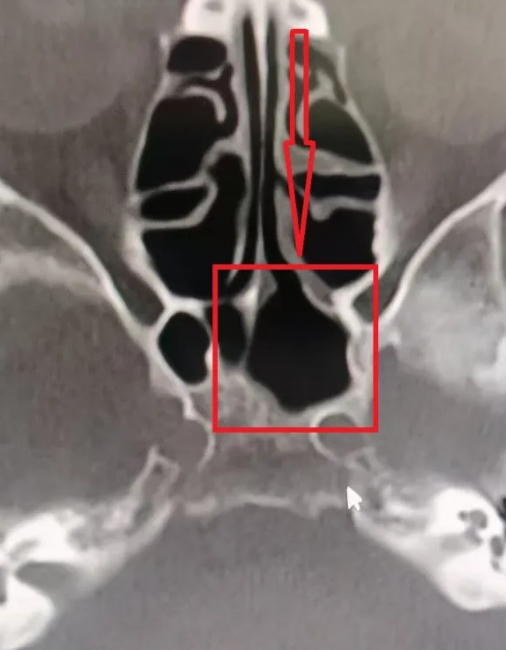

反复折腾几次之后,再次头疼难忍的她来到了徐州和平医院内科,接诊医生询问病史,进行专科查体后,考虑鼻窦炎可能,予以CT检查,结果印证了这一猜想:蝶窦腔内炎症,真菌性感染不除外,结合临床,建议林奶奶到耳鼻喉科就诊。

进一步在耳鼻喉科门诊进行检查后,最终确认为“真菌性蝶窦炎”,林奶奶的蝶窦腔内确实存在疑似真菌团块大量填充,而这,就是她头痛的罪魁祸首。

前后对比

治疗后